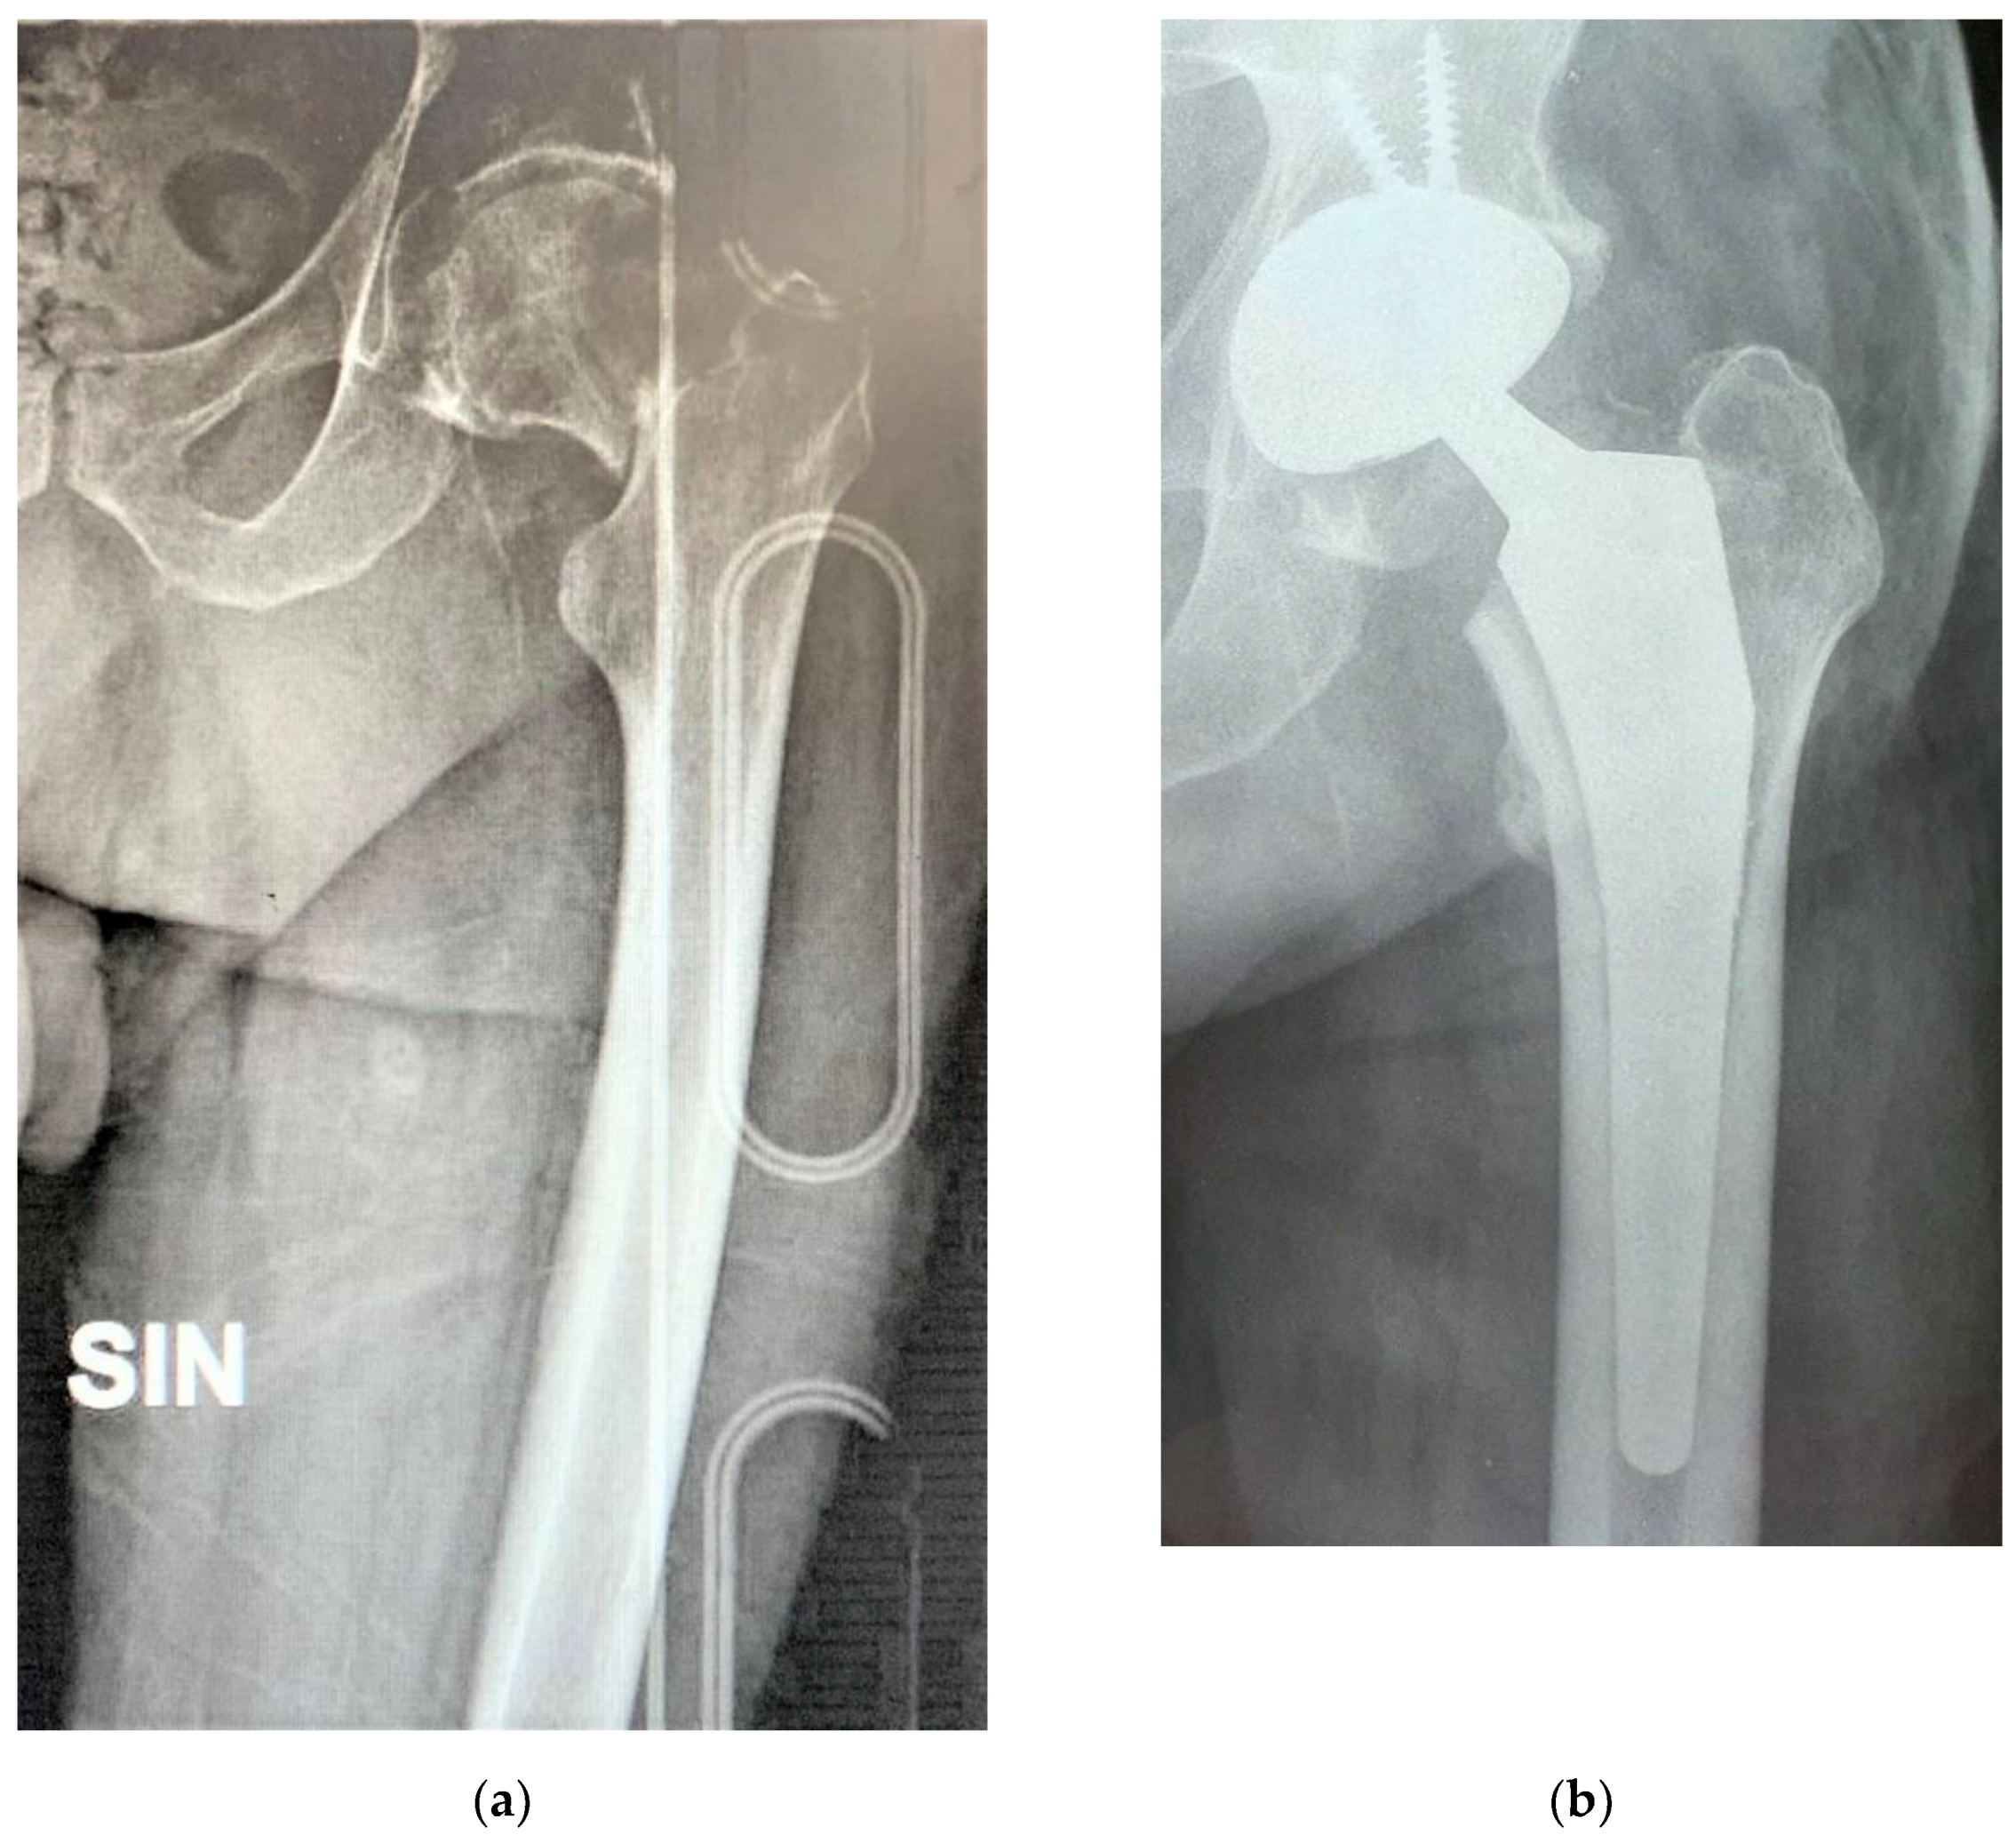

Figure 2 shows the case of a 54 years old male who was admitted to our hospital due to a displaced fracture of his left femoral neck and was in treatment since several years for depression, treated with the G7 modular cementless DM cup with 2 screws and a Taperloc stem on the femoral side.

Figure 2. Displaced fracture of left femoral neck in a 54 years old male (a); dual mobility (DM) modular cup with screw and cementless stem (b).